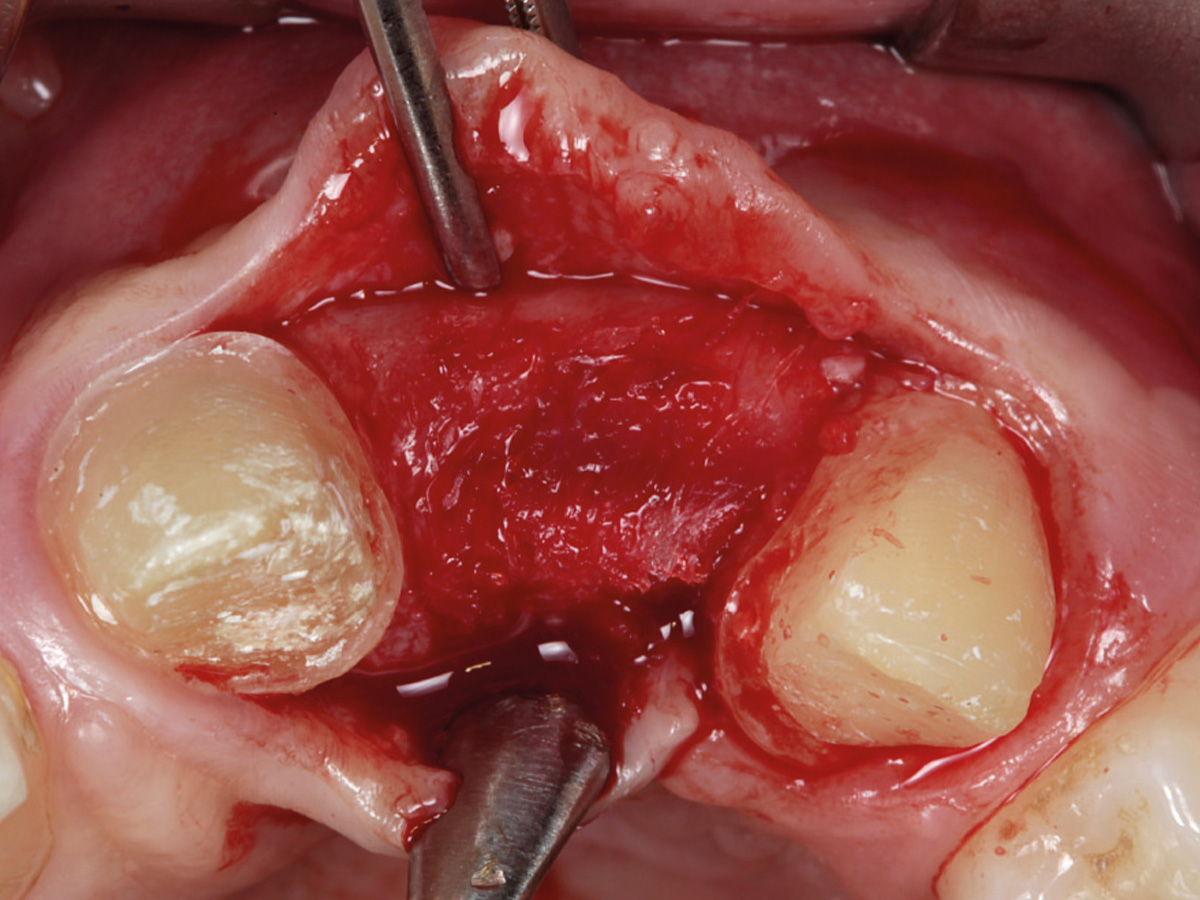

Abbildung 3

Nach Bildung eines Mukoperiostlappens wird mit der Bone Lamina die bukkale Lamelle rekonstruiert. Die Lamina wird mit Titanpins befestigt.

Abbildung 4

Der Defekt wird mit mp3® augmentiert.